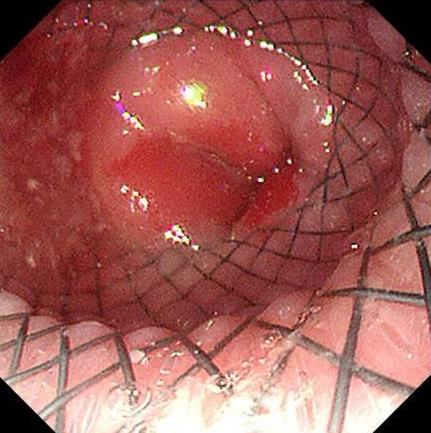

• 食管静脉曲张患者内镜诊疗过程中血栓头脱落出血的危险因素分析及风险预测模型构建

摘要:目的 探讨食管静脉曲张患者内镜诊疗过程中血栓头脱落出血的危险因素,并构建其风险预测模型。方法 回顾性分析2009年2月-2024年7月该院行内镜检查发现食管静脉曲张伴血栓头形成的患者209例,根据内镜诊疗过程中是否发生血栓头脱落出血,分为:未脱落组(186例)和脱落组(23例)。比较两组患者临床特征和内镜特征,将单因素分析中差异有统计学意义的因素纳入多因素Logistic回归分析,探讨其独立危险因素。通过R语言软件构建列线图风险预测模型,并评价其预测效能。结果 多因素Logistic回归分析显示,血栓头颜色为红色(OR^ = 6.231,95%CI:1.748~22.208)、血栓头直径 ≥ 3 mm(OR^ = 4.355,95%CI:1.341~14.144)、血栓头形状为锥形(OR^ = 8.555,95%CI:2.427~30.154)和胃内存在积血(OR^ = 7.079,95%CI:1.665~30.103)是内镜诊治过程中血栓头发生脱落出血的独立危险因素。Nomogram列线图预测模型的敏感度为0.870(95%CI:0.732~1.000),特异度为0.887(95%CI:0.842~0.933)。结论 血栓头颜色为红色、形状为锥形、直径 ≥ 3mm和胃内有积血是影响内镜诊疗过程中血栓头脱落出血的独立危险因素,应针对以上因素及时干预,以预防术中血栓头脱落出血。